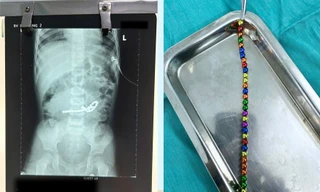

TPO - Trong lúc chơi các viên nam châm, bé trai vô tình nuốt vào bụng và phải nhập viện cấp cứu. Bằng phương pháp nội soi, các bác sĩ đã phải xẻ ruột bệnh nhân để lấy các viên nam châm nhằm tránh nguy cơ tắc ruột, thủng ruột cho bệnh nhi.

TPO - Ngày 19/9, BS Nguyễn Hiền, khoa Ngoại Tổng hợp, Bệnh viện Nhi Đồng 2 TPHCM cho biết, tại đây vừa tiếp nhận và can thiệp cho trường hợp trẻ bị thủng ruột, nguy hiểm tính mạng vì nuốt nam châm đồ chơi.

TPO - Trẻ ngậm trong miệng rồi nuốt lúc nào không biết, đến khi đau đớn quằn quại phải nhập viện thì đã bị thủng ruột bởi 2 viên bi nam châm gây ra. Bác sĩ cảnh báo, nuốt dị vật là tai nạn rất nguy hiểm có thể cướp đi sinh mạng của bệnh nhi.